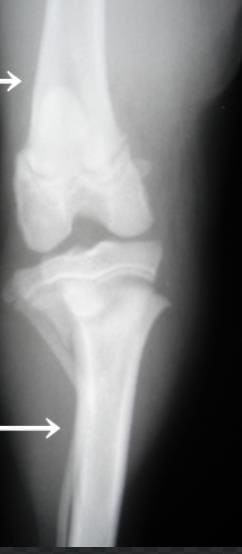

무릎뼈 확인

먼저 발이 닿지 않는 의자에 앉은 후 무릎뼈를 꾸욱 눌러보시길 바랍니다. 이때 무릎뼈와 다리 사이에 있는 연골의 있어 헷갈릴 수 있는 만큼 예민하게 살펴보시길 바랍니다.

만약 성장판이 닫힌 어른의 경우라면 말랑거리고 안으로 들어가지만 그렇지 않은 아이의 경우 조금 다른데요. 약간의 딱딱함이 느껴진다면 성장판이 아직까지 열려 있다고 생각하실 수 있습니다.